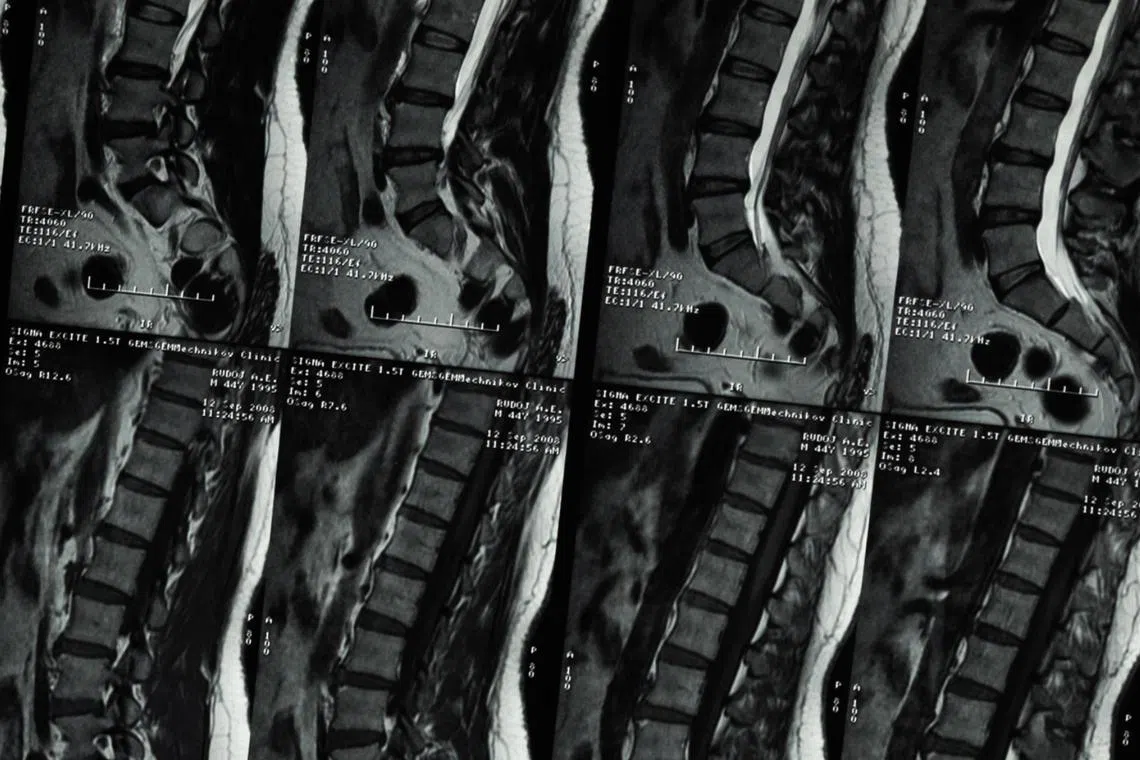

SINGAPORE - Scoliosis is a sideways curvature of the spine that when viewed on an X-ray, appears like an “S” or a “C” shape than a straight line.